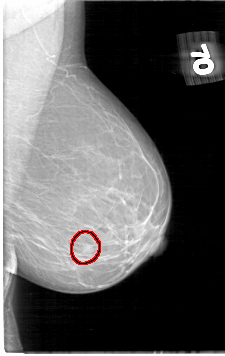

D_4060_1.RIGHT_MLO

LEFT_MLO LINES 5326 PIXELS_PER_LINE 3361 BITS_PER_PIXEL 12 RESOLUTION 43.5 OVERLAY

FILE: D_4060_1.LEFT_MLO.OVERLAY

TOTAL_ABNORMALITIES 1

ABNORMALITY 1

LESION_TYPE MASS SHAPE ROUND MARGINS OBSCURED

ASSESSMENT 0

SUBTLETY 4

PATHOLOGY BENIGN

TOTAL_OUTLINES 1

BOUNDARY